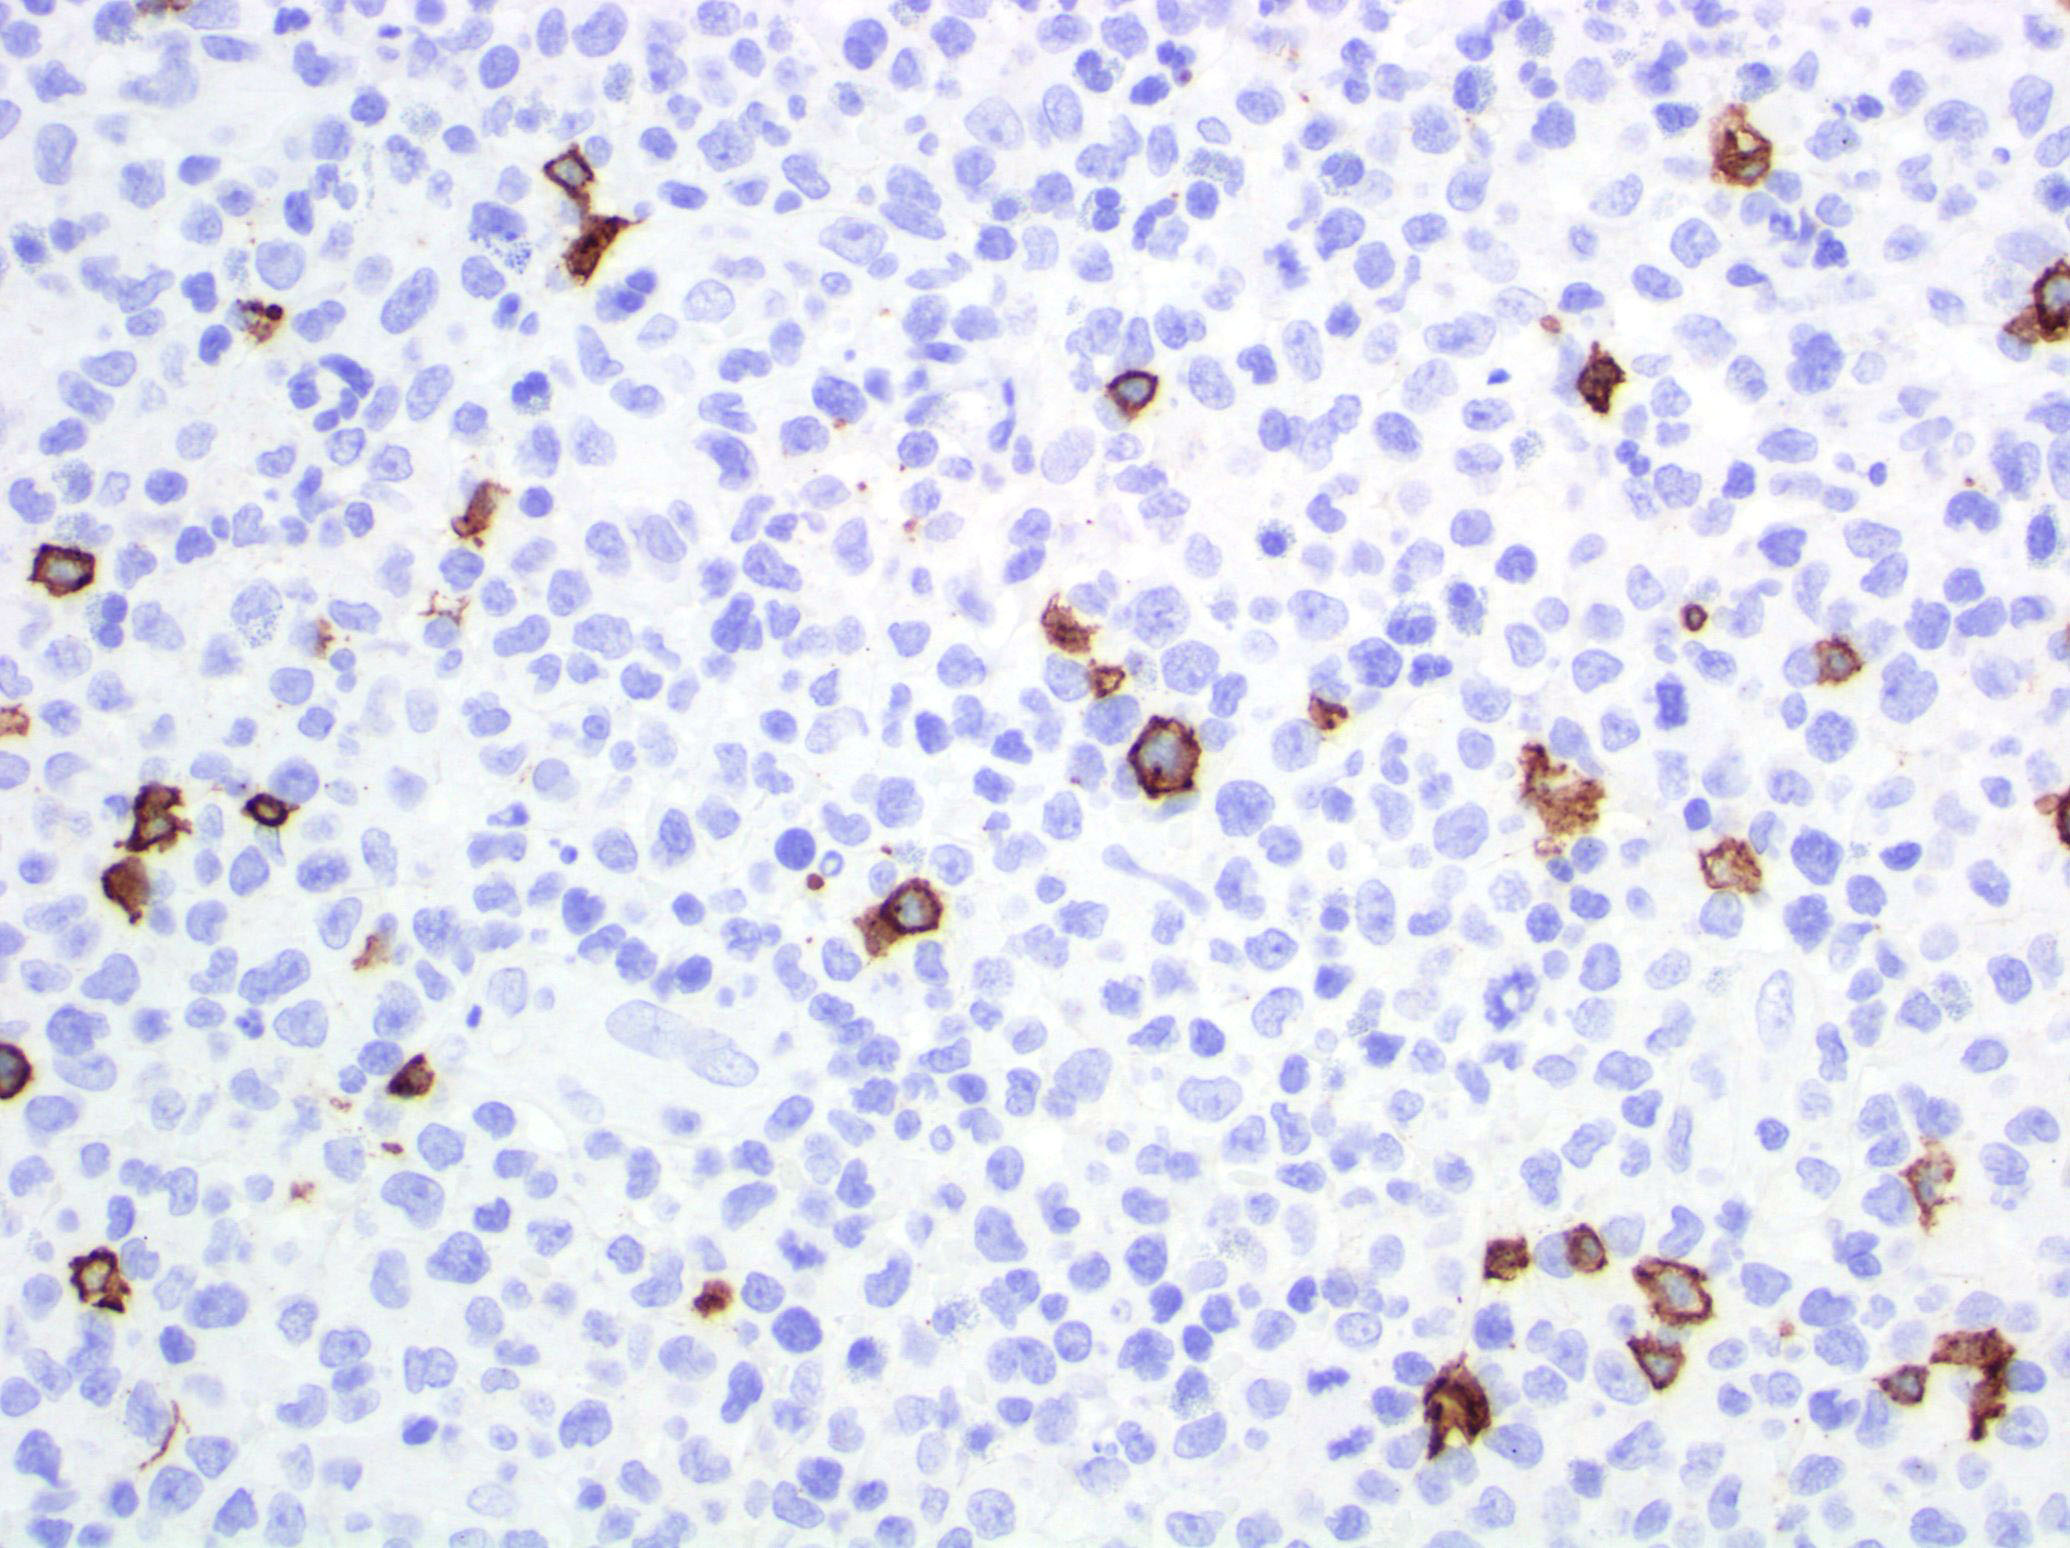

- Type A: wedge shaped and extensive lymphoid infiltrate with neutrophils, eosinophils and histiocytes; CD30+ cells are scattered and the overall histologic appearance mimics classic Hodgkin lymphoma

Microscopic (histologic) images

Contributed by Roberto N. Miranda, M.D.